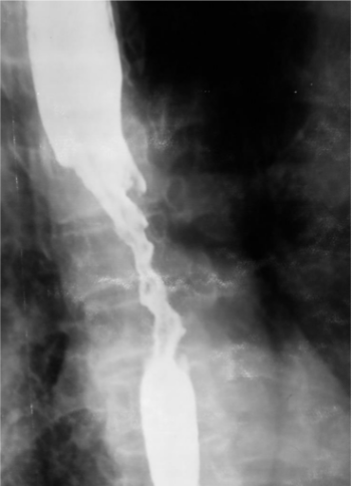

What is this

Esophageal ca